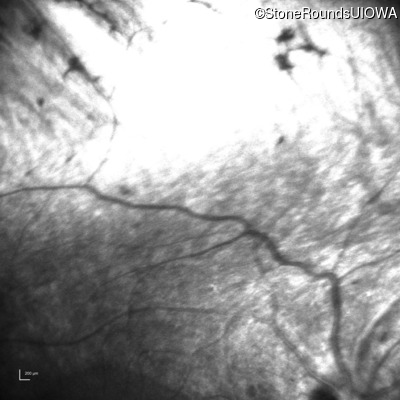

Infrared Fundus Photograph - Left - No Light Perception

Exemplar